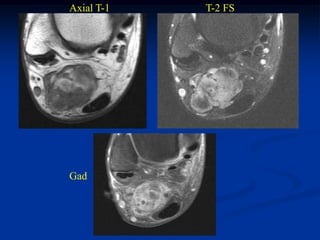

Case #1196.2 Ossifying Lipoma Cor T-1 Axial T-2 53 yr male with painless mass in knee for 3 yrs

• 116.